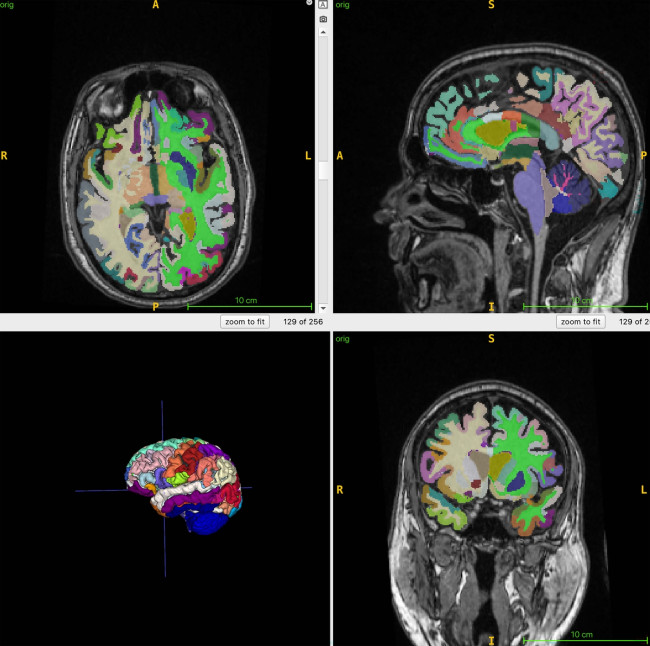

뇌 나이 추정을 위한 뇌 MRI 영상 [Cyrus Raji, M.D., Ph.D., and RSNA 제공. 연합뉴스 사진]

뇌 나이 추정을 위한 뇌 MRI 영상 [Cyrus Raji, M.D., Ph.D., and RSNA 제공. 연합뉴스 사진]

미국 워싱턴대 의대 사이러스 라지 박사팀은 25일 전신 MRI로 건강한 성인 1천100여명의 근육과 지방, 뇌 조직을 촬영하고, 총근육량과 내장지방, 피하지방, 뇌 나이 간 관계를 인공지능(AI)으로 분석한 결과 근육량이 많고 내장지방 대비 근육 비율이 낮으면 뇌 노화 속도가 느린 것으로 나타났다고 밝혔다.

연구팀은 이 연구에서 뇌의 구조적 MRI 영상의 부위별 부피를 기반으로 추정한 뇌 나이와 전신 MRI로 측정한 총근육량과 내장지방, 피하지방 사이의 연관성을 인공지능 알고리즘으로 분석했다.

이들은 4개 지역 거주자 1천164명(평균 나이 55.17세)을 대상으로 전신 MRI를 촬영하고 이를 지방과 체액, 근육 등이 다른 색으로 보이게 하는 기법과 결합해 총근육량과 내장지방 피하지방, 뇌 나이를 정량화했다.